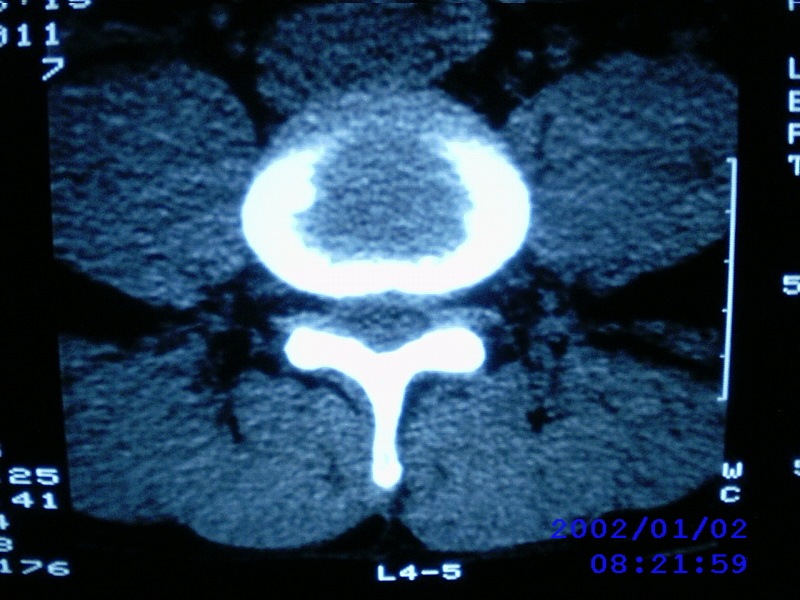

患者,男性,40岁,腰痛伴左下肢疼痛、麻木6年。5年前做过腰椎间盘手术,具体是哪个位置病人记不清了。

我拍的是l4-5、l5-s1

1)l4/5及l5/s1左侧椎板术后改变。2)l5/s1椎间盘突出,l5椎体下缘许莫氏结节。3)l4/5椎间盘膨出并突出。4)l3/4椎间盘膨出。

1)l4/5及l5/s1左侧椎板术后改变。2)l5/s1椎间盘突出,l5椎体下缘许莫氏结节。3)l4/5椎间盘膨出并突出。